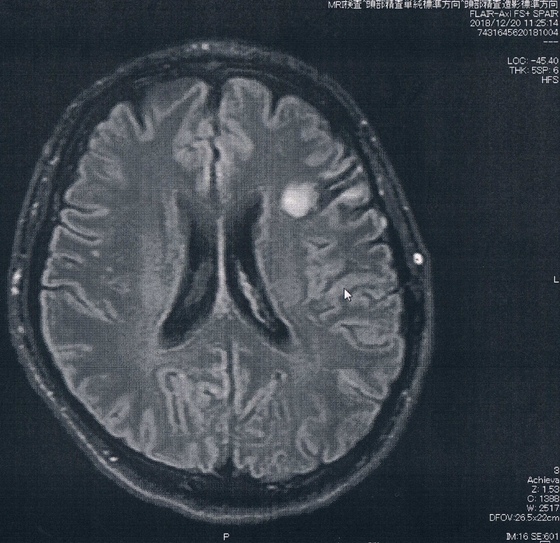

MRI検査の結果、半年前と比べても変化は無いように見えるが、

一年前やそれ以前の画像と比べると若干変化があるようにも見える。

と先生が言う。

結果から言って、造影剤の入り込みも無く悪性転化は無いとのこと。